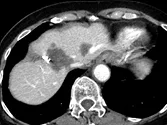

Figure 9. Métastases hépatiques d’un cancer du colon. Récidive après résection

chirurgicale traitée par association contenant du bévacizumab.

A. Examen initial et B, examen après quatre cures. En comparant ces deux coupes

acquises au temps portal après injection, on voit la quasi disparition

du rehaussement après traitement. Malgré l’absence de changement du grand

diamètre, c’est un signe de l’efficacité antio-angiogénique de la thérapie ciblée